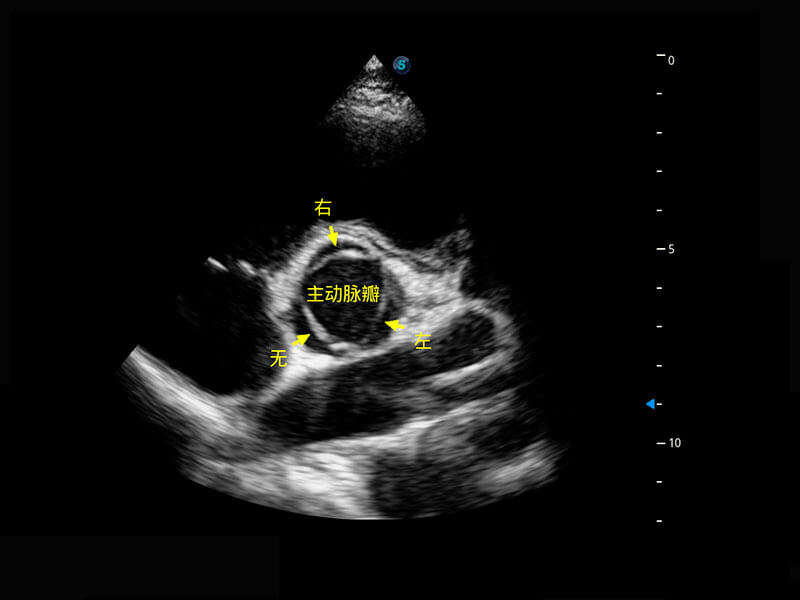

P60搭载一系列胎儿心脏成像技术,实现精细的胎儿心脏评估。

四腔切面

右室双出口

胎心容积成像